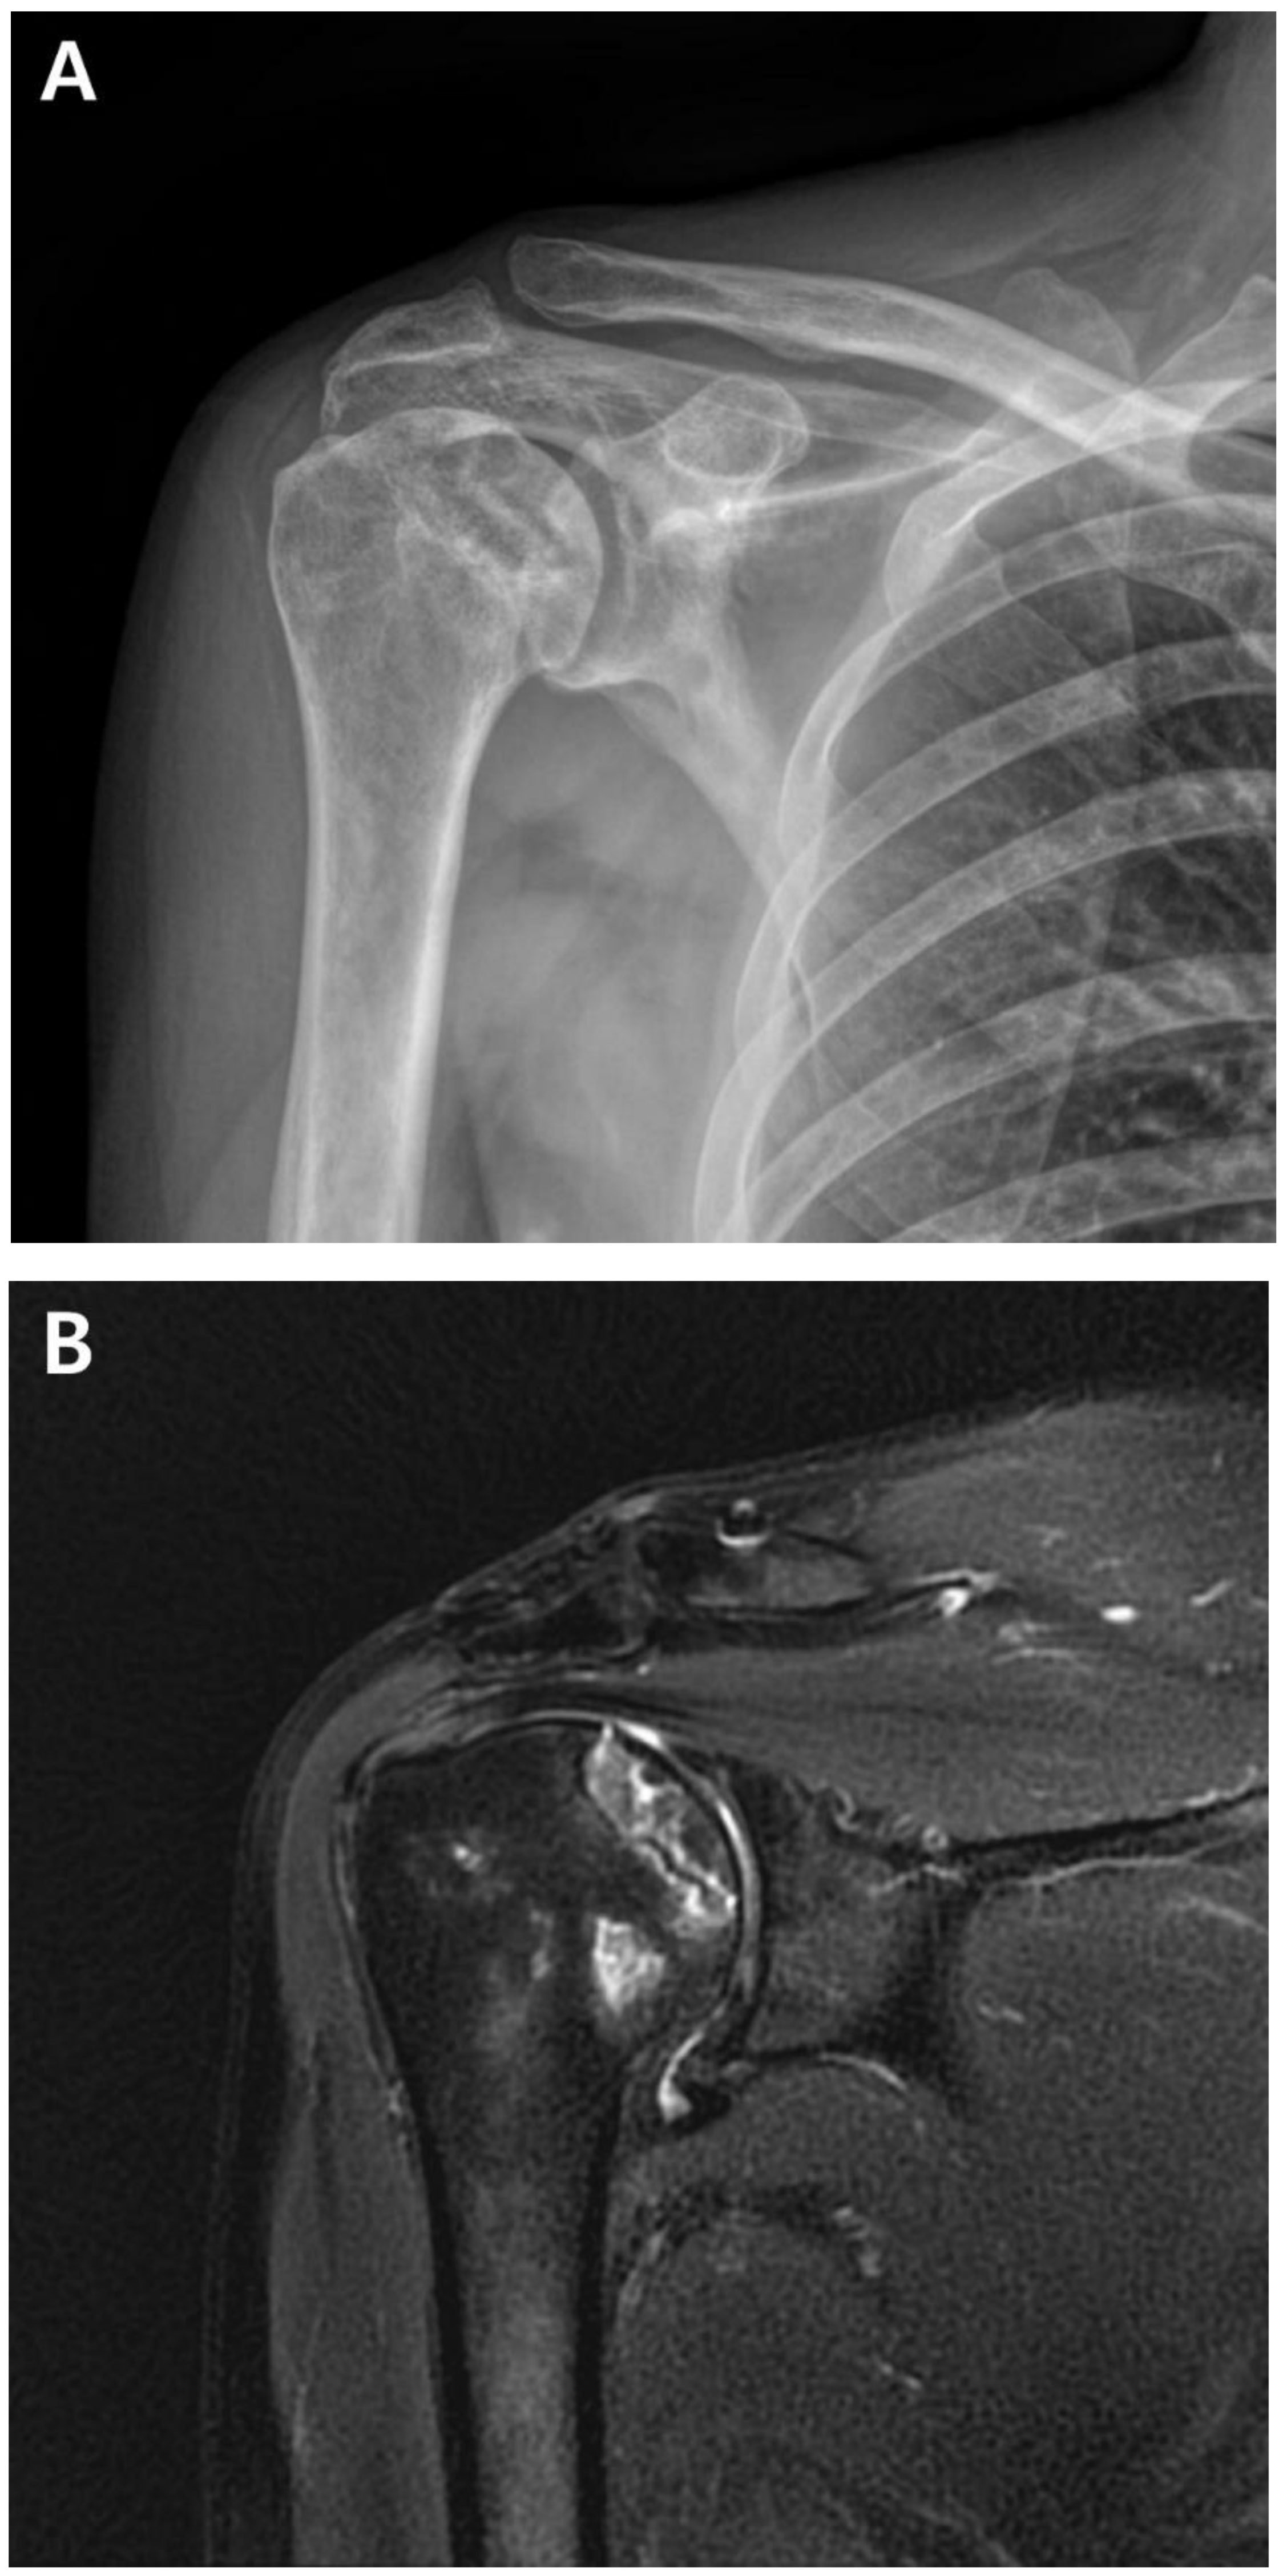

A postoperative scar was observed on the superior aspect along the distal clavicle and acromion, without definite tenderness, swelling, or redness. Preoperatively, the ROM of the affected shoulder was 90° for active forward flexion, 90° for abduction, 40° for external rotation, and sacral level for internal rotation. The visual analog scale (VAS) score was 4, the American Shoulder and Elbow Surgeons (ASES) score was 51, and the Constant-Murley Score (CMS) was 48. Preoperative shoulder radiographs showed acceptable alignment and joint congruency, with no bony spurs or subchondral lesions. Anteroposterior and axillary views of the shoulder radiograph showed acceptable status of acromioclavicular joint reduction without arthritic changes. Magnetic resonance imaging (MRI) showed incomplete signal changes in the supraspinatus muscle, with preserved structural integrity (Fig. 1). Given the patient’s persistent symptoms, which did not improve, the patient had opted for ACR, with informed consent.

Figure 1. A. Preoperative plain anteroposterior radiograph. Acromioclavicular joint alignment was acceptable with no arthritic changes. The glenohumeral joint showed adequate joint space and congruency. B. Oblique coronal T2 fat-suppressed magnetic resonance imaging (MRI). MRI of the right shoulder showed a thickened axillary pouch with normal hypointense joint capsule. The supraspinatus tendon had high signal variation with intact continuity.